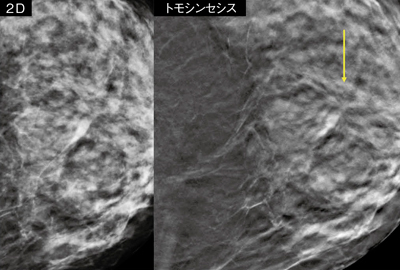

■症例2:50歳代,女性,検診発見例

2D画像(左)では,病変の認識はできない。トモシンセシス画像(右)では,構築の乱れ,スピキュラが認識可能である(C-4)。